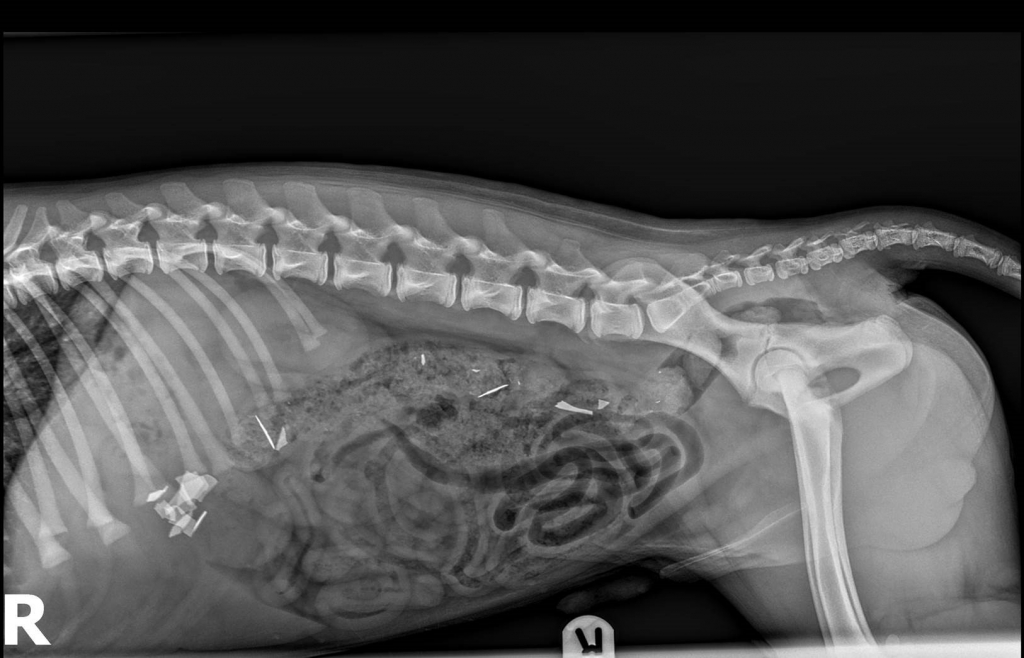

A specialist at one of the UK’s leading small animal hospitals has explained why doing ‘nothing’ was the best course of treatment for a four-month-old puppy that had swallowed razor blades.